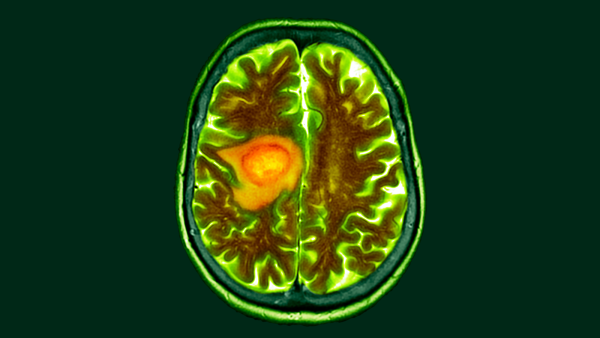

Дослідження на мишах показують, що дієта з високим вмістом клітковини може допомогти підтримувати функцію імунних клітин, які виявляють та знищують рак. (Зображення: CHRISTOPH BURGSTEDT/SCIENCE PHOTO LIBRARY via Getty Images)